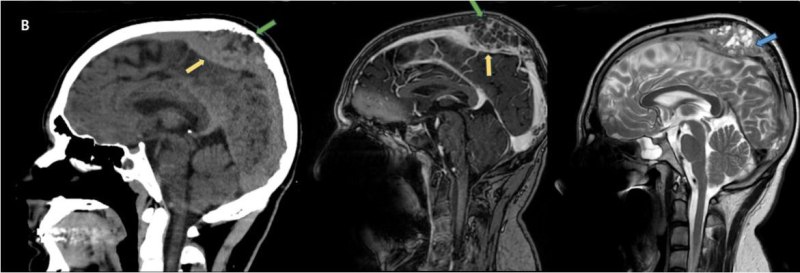

- A) Vertekste, orta hatta, multikistik, T2A sekanslarda yoğun içerikli sıvı-sıvı seviyelenmesi (oklar) ve T1A sekanslarda hiperintens, SWI sekanslarda blooming artefaktı oluşturan, belirgin düşük ADC değerlerine sahip, kanama alanları içeren (oklar) kitlesel lezyon mevcuttur.

- B) Parietal kemik iç tabulada erozyon (oklar), süperior sagital sinüste inferiora yer değiştime ve invazyon (oklar) ve lezyonda heterojen kontrastlanma izlenmektedir.

- MR görüntülemede genellikle T1 ağırlıklı görüntülerde gri cevher ile izointens, T2 ağırlıklı görüntülerde hiperintens, heterojen kontrast tutulumu gösteren kitlesel lezyon izlenir. Nekrotik, hemorajik, kistik alanlar içerebilir. Kanamaya bağlı sıvı-svı seviyeleri izlenebilir.

- İntrakraniyal uzanımı bulunan lezyonlarda dural kalınlık artışı ve komşu parankimde perilezyoner ödem izlenebilir.